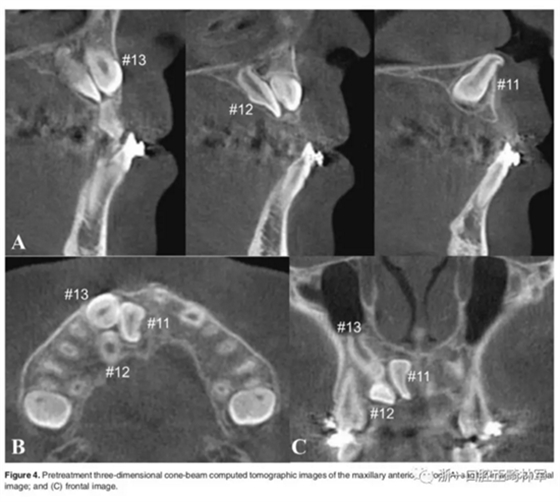

影像檢查:

全景X片及CBCT示:11-13復雜阻生,上頜前牙區(qū)牙槽骨水平不足;11阻生,遠中旋轉90°,牙冠朝向腭側,根尖位于鼻底、前鼻棘皮質骨內,牙根形態(tài)彎曲;12、13不完全易位,12位置偏腭側,13位置偏舌側,12的牙根形態(tài)也較彎曲。